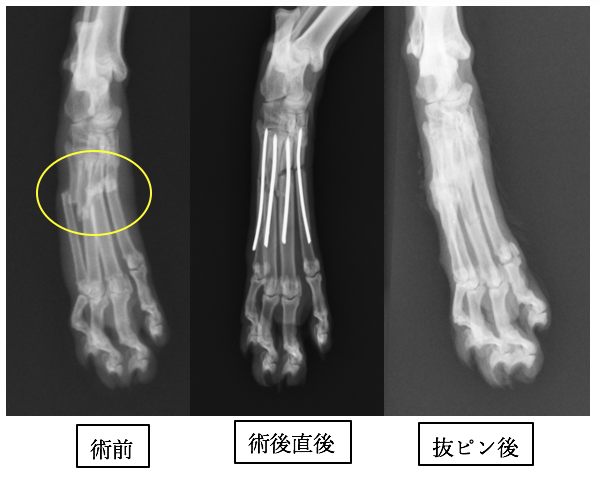

1本が折れてしまっています。特に第3指、第4指が折れた場合には手術適応で、プレートを入れた場合は外固定が必要なくなります。1.1mmのプレートスクリューを使用しています。